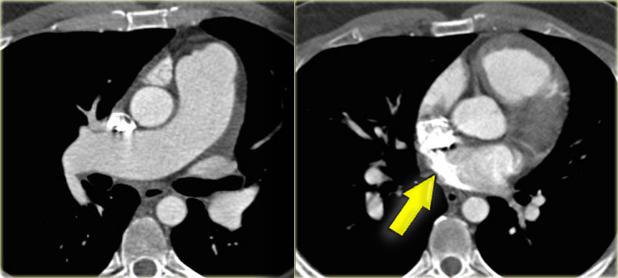

On the left preoperative and postoperative MDCT studies of a 2-month-old female infant with double aortic arch presenting with stridor and repeated apnea.

The smaller left arch is partially resected.